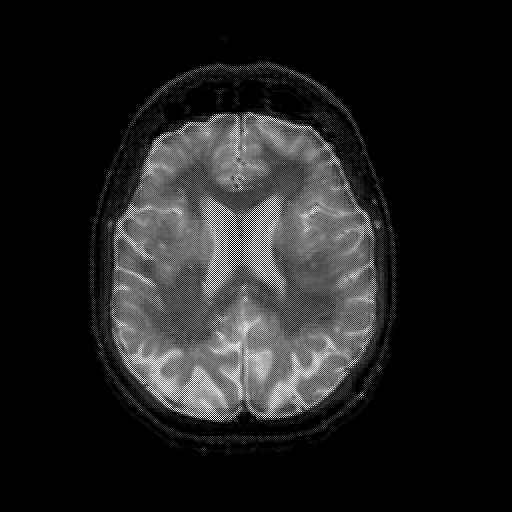

overlay 1: Slice 34

Slice 34

MRCBFCBF with

T1PDT2T1PDT2